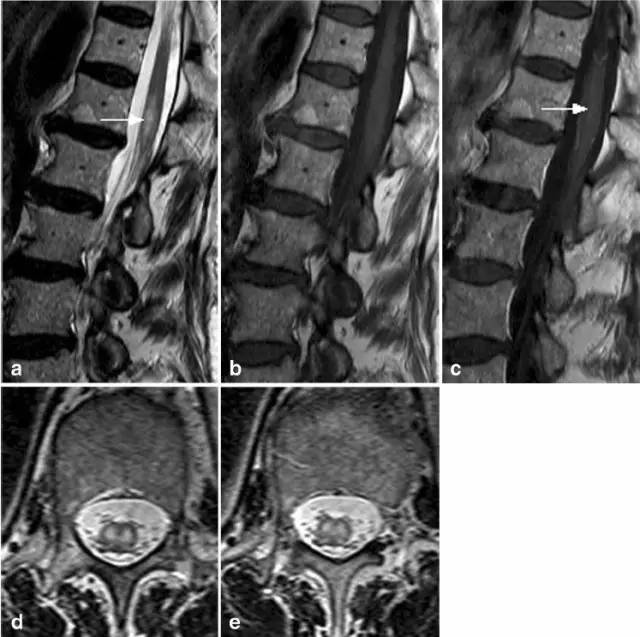

病例10:52岁女性。Th10/11-L1水平T2高信号伴水肿(图a,c),增强T1显示(图b为发病5天,图e和f为发病10天)马尾前强化影(positive anterior cauda equine sign,图d箭头)